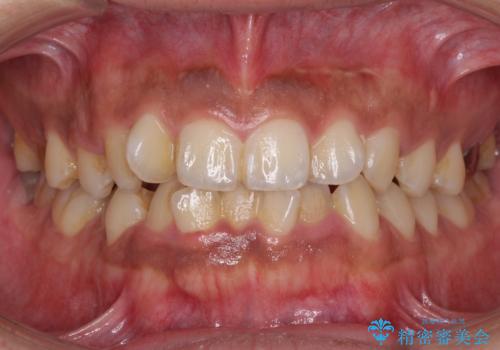

- 前歯のデコボコを気にして来院された患者様です。

前歯が90度近く捻れていたため、しっかりと治すことを考えるとワイヤー矯正の方がおすすめではありましたが、本人の希望によりインビザラインを用いて矯正治療を行うこととしました。

途中2年強の来院がなく、改善されていたデコボコが元に戻ったり、装着時間が不足しており前歯のデコボコは十分に改善することはできませんでしたが、5年間の有効期限内で可能な限り歯列を整えることができました。